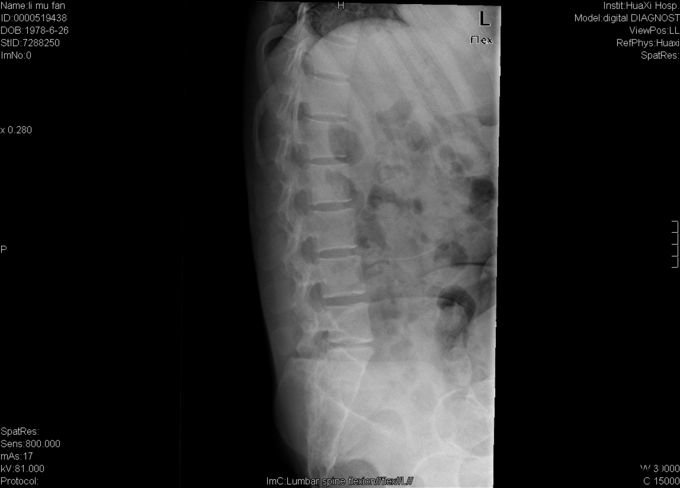

女,37岁4月,因“反复腰痛伴左下肢疼痛20+年,加重1+月”入院。20+年前患者因跌倒都出现腰部疼痛,症状反复发作,偶伴左小腿疼痛,予以牵引、针灸、按摩等治疗后症状缓解,久坐后复发。1+月前再次出现腰部及臀部疼痛,于当地医院予以对症支持后症状未完全缓解,现为求进一步治疗,遂入我院就诊。

专科检查:视:步入病房,步态无明显异常。腰椎生理弧度浅直,无明显侧弯,四肢及关节屈伸活动正常。触:脊柱腰段无明显叩痛,L4-L5、L5-S1椎旁叩痛,左臀广泛压痛,右踝外侧感觉减退,双下肢及鞍区无明显皮肤感觉减退及过敏。动量:双下肢肌力、肌张力正常,病理征(-),双侧跟腱反射正常,其他生理放射正常,余未见明确异常动量。 辅助检查:外院MRI:腰5/骶1椎间盘突出,腰5、骶1椎体异常低信号。。

初步诊断:腰5/骶1腰椎间盘突出症伴不全神经损害